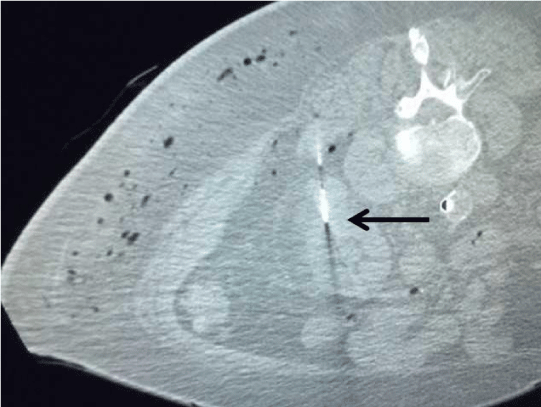

A 17- gauge, 20 cm Neuwave PR probe (NeuWave Medical, Madison, WI) was used for the procedure. After the probe was placed with its tip in the tumor via left posterolateral approach under ultrasound guidance (Figure 2), a CT scan to check position of the probe with tissue-lock revealed a large amount of air in the left flank subcutaneous tissues as well as left perinephric free air (Figure 3). The microwave ablation probe was immediately taken out of the patient. Using Seldinger technique with an 18-gauge needle, an 8 French pigtail drainage catheter was placed into the left flank subcutaneous tissues over an Amplatz guidewire (Figure 4) and the CO2 was aspirated. Subsequently, an 18-gauge needle was advanced into the left perinephric space under CT guidance and a small to moderate volume of the CO2 was aspirated. The ensuing CT scan demonstrated interval decrease in amount of CO2 in the left flank subcutaneous and left perinephric space. The subcutaneous pigtail drainage catheter was removed while the patient was still on the CT table.

Figure 4: Placement of an 8-Fr. pigtail catheter (arrow) into the left subcutaneous space for evacuation of gas.